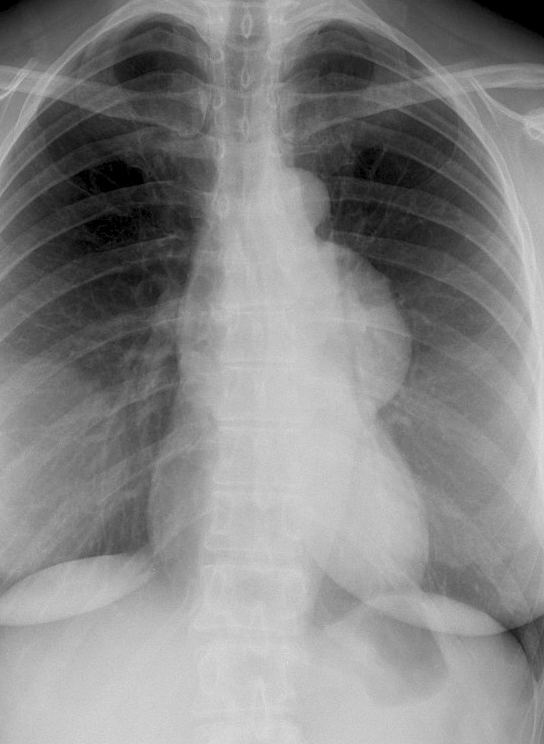

Thymoma